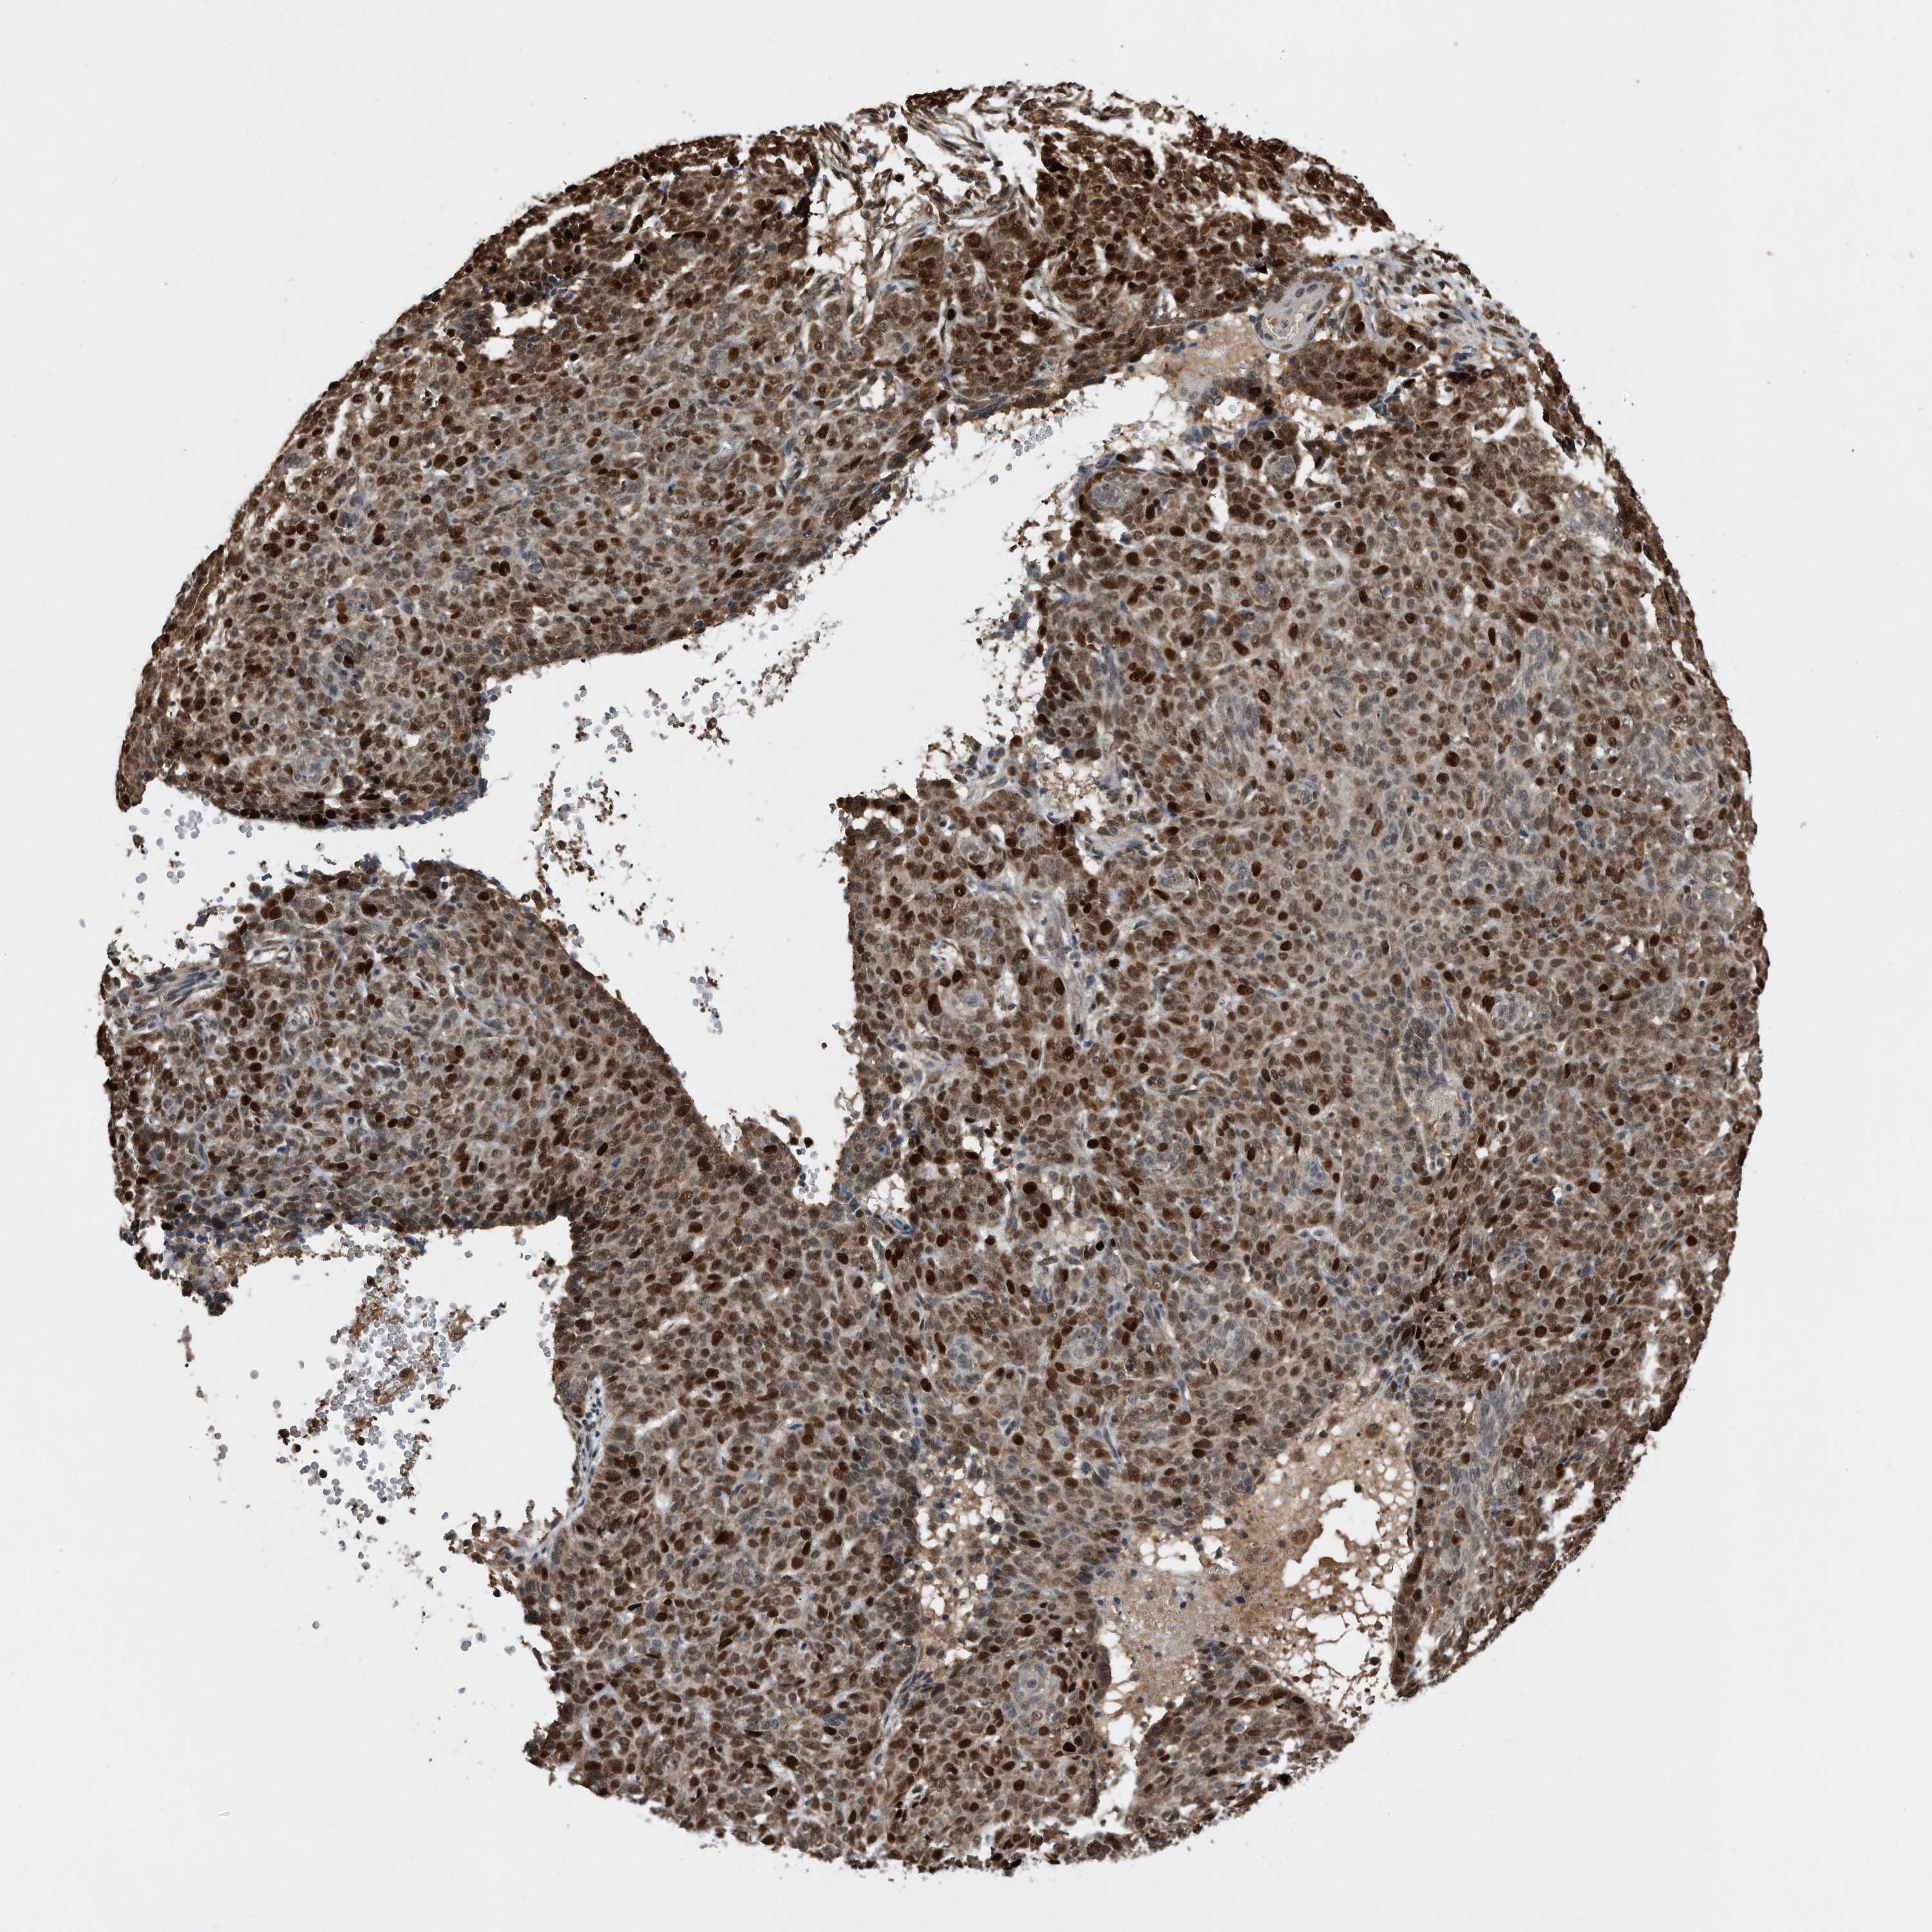

CANCER SKIN CANCER Show tissue menu

Basal cell and squamous cell cancer

SKIN CANCER - Protein expressioni

A mouse-over function shows sample information and annotation data. Click on an image to view it in a full screen mode. Samples can be filtered based on level of antibody staining by selecting one or several of the following categories: high, medium, low and not detected. The assay and annotation is described here.

Each image is clickable and will lead to virtual microscopy that enables deeper exploration of all samples and also displays staining intensity scores, fraction scores and subcellular localization as well as patient and tissue information for each sample.

HPA030521

HPA030522

HPA030523

CAB000148

CAB080240

CAB080241

CAB080242

Staining

High

Medium

Low

Not detected

Intensity

Strong

Moderate

Weak

Negative

Quantity

>75%

75%-25%

<25%

None

Location

Nuclear

Cytoplasmic/membranous

Cytoplasmic/membranous,nuclear

Basal cell carcinoma

Squamous cell carcinoma, NOS

Squamous cell carcinoma, metastatic, NOS